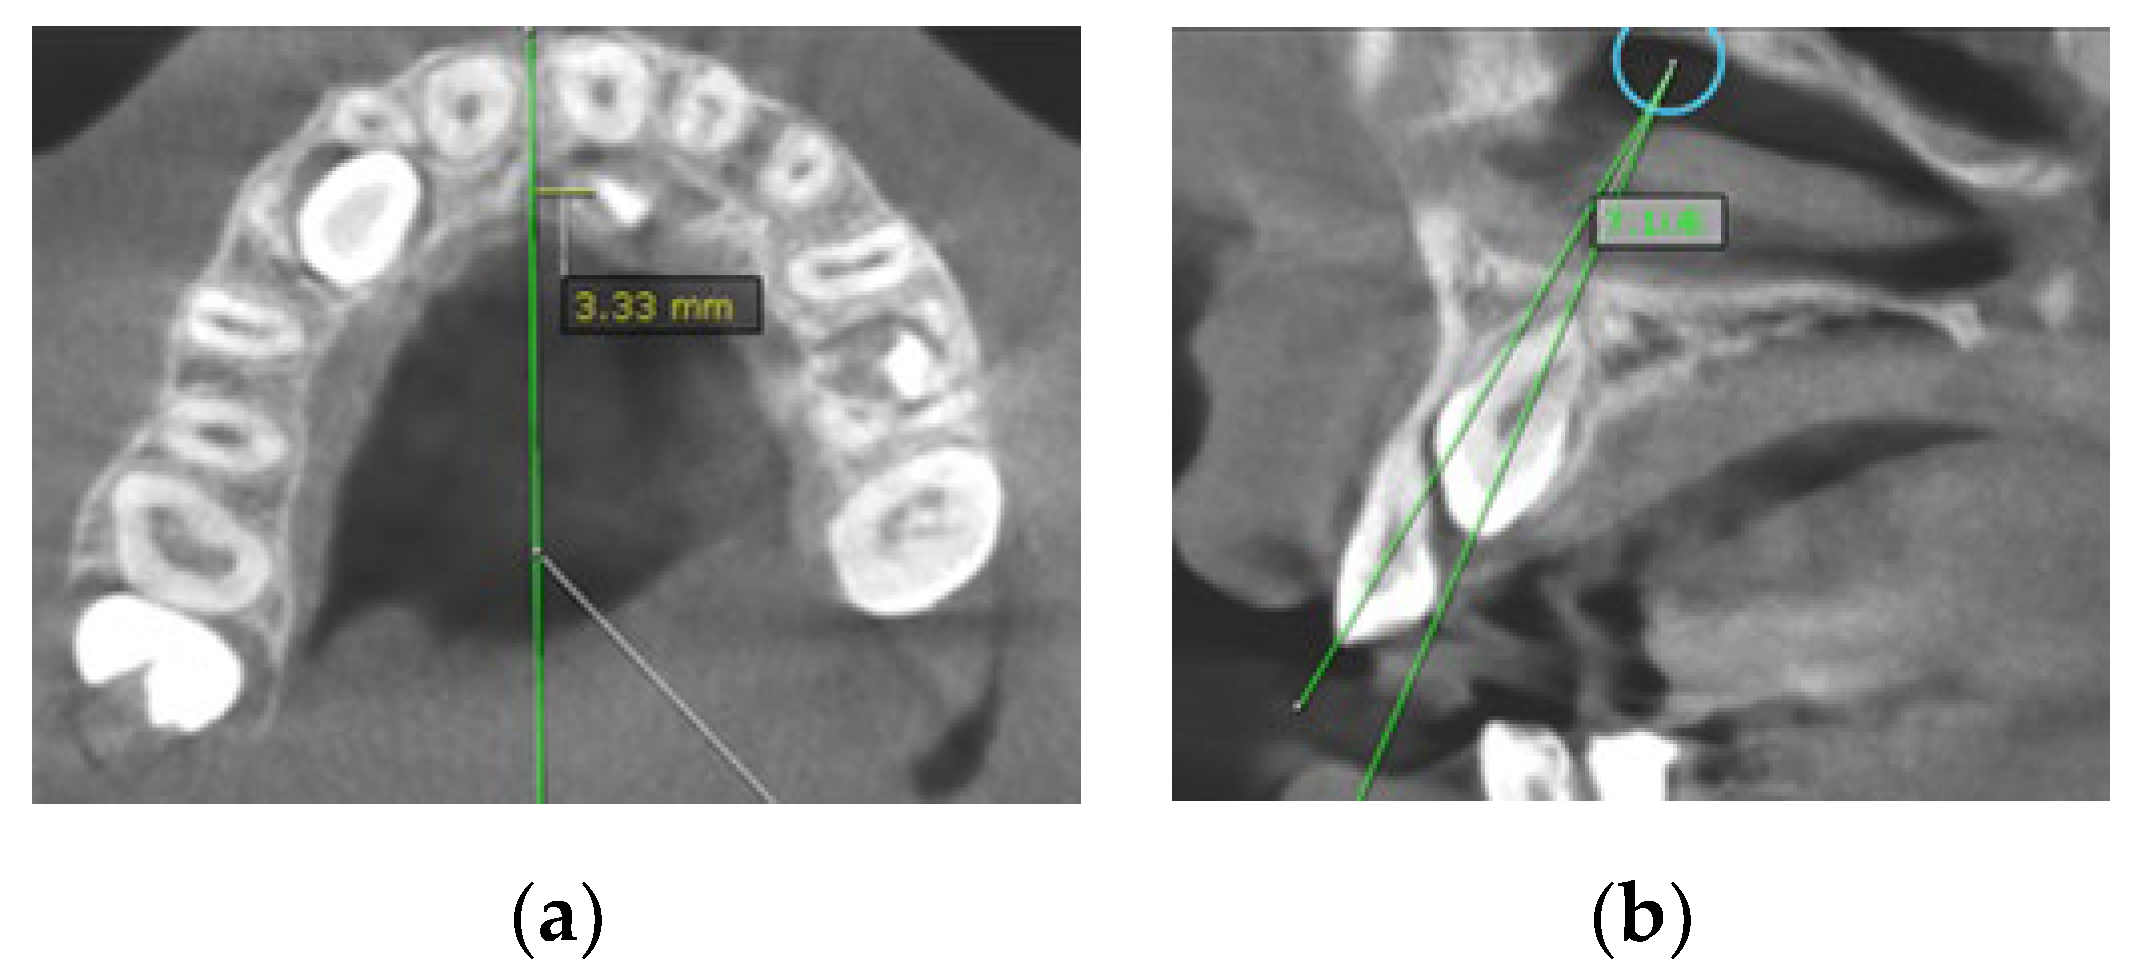

- Distance of the impacted maxillary canine cusp to the midline (measured on axial CBCT scans) (Figure 2a);

Figure 2. (a) The distance of maxillary canine cusp to midline (measured on CBCT images in axial plane); (b) Angle between long axis of impacted maxillary canine and long axis of adjacent lateral incisor measured on CBCT images in sagittal plane.Figure 2. (a) The distance of maxillary canine cusp to midline (measured on CBCT images in axial plane); (b) Angle between long axis of impacted maxillary canine and long axis of adjacent lateral incisor measured on CBCT images in sagittal plane.

- Angle between the longitudinal axis of the impacted maxillary canine and the long axis of the adjacent central/lateral incisor (measured on CBCT images in the sagittal plan) (Figure 2b);

In the group with RR, the average angle between the impacted canines and midline was 46.7°, and the average angle between the impacted canines and the adjacent lateral/central incisors was 43.1°/40.3°. The average angle between the canine and occlusal line was 43.6°, whereas the average angle in the group with no resorptions was 55.8° (Table 3). Based on the clinical findings in the group of subjects with RR on the incisors, the angulation of the impacted canine to the midline and angulation to the incisor were found to have significantly higher values than in the group of subjects with no resorption. On the other hand, the angulation of the impacted canine to the occlusal line was found to be lower than in subjects with no resorption, and it was statistically confirmed (Figure 2).